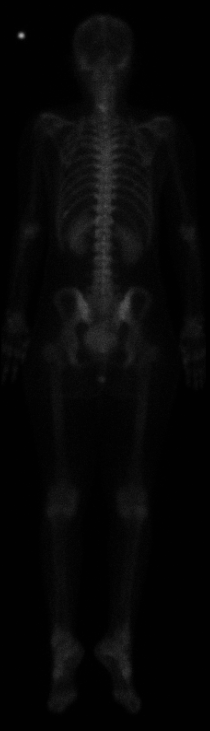

When a pain starts,and doesn't go away....after awhile you know something's wrong and then you submit to the testing. The technician running the bone scan said "{pause} good luck with everything," my husband calling with the report he picked up "{pause} it's not good..." my oncologist calling after my husband called about what to do next "I wish I had good news, but I need more pictures to see what's going on..." and the wording from the bone scan results all add up. It is no good. MRI tomorrow....I think it's time to make plans to travel the world before this thing does me in. Here are my bone scan pictures (not high quality, but you can see the brightness on the neck).

Back: